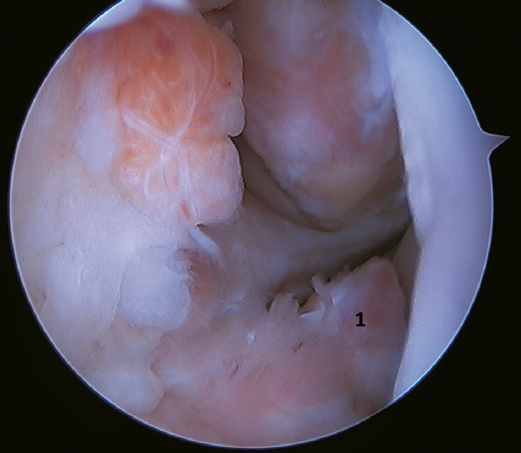

Another point of interest is the presence of os subfibulare. In these cases, we have the option of fixation, although this is usually not feasible and the best therapeutic option is excision and reconstruction, due to the impossibility of direct repair(60) (Figure 4).

Rotational instability is a relatively novel concept introduced in 2011 by Buchhorn(67), describing combined injuries of the lateral complex and deltoid ligament, and an anatomical reconstruction technique for both injuries. Although there is no biomechanical evidence as to why medial injury occurs in patients who have not suffered eversion trauma, it is likely that the stress maintained on the medial complex in lateral instability may evolve into rotational instability - which is in line with the previously commented domino effect theory (5,62). It is estimated that up to 10-15% of all cases of CLAI may progress to injury of the medial complex, especially affecting its most anterior fibers. Recently, Vega(68) described the combination of injuries of the lateral complex with the "book-page" injury (Figure 7) of the superficial tibiotalar fascicle of the deltoid ligament, due to excessive internal rotation in chronic lateral instability, and its treatment through direct repair of both lesions. Acevedo(34) and Vega(68) also described the safety position of the anchors in the medial malleolus.

Figure 5. Tearing of the anterior talofibular ligament and calcaneofibular ligament with poor tissue quality of the ligament remnant.